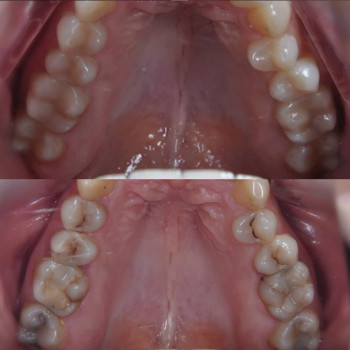

Основна спеціальність: Стоматолог

Ключові напрямки: стоматологія

Послуги і ціни доктора Ігор Киселиця (13)

| Стоматологія (13) | |

| Діагностика зубів | ✔️ |

| Лікування зубів | ✔️ |

| Лікування карієсу | ✔️ |

| Лікування каналів | ✔️ |

| Лікування зубів | ✔️ |

| Лікування пульпіту | ✔️ |

| Установка пломби | ✔️ |

| Тимчасова пломба | ✔️ |

| Пломбування каналів | ✔️ |

| Лікування ясен | ✔️ |

| Видалення зубів | ✔️ |

| Видалення молочного зуба | ✔️ |

| Видалення зуба мудрості | ✔️ |